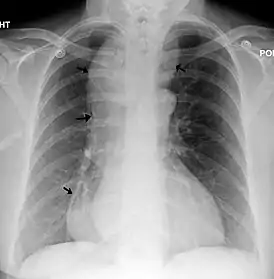

- Рентгенография с контрастированием пищевода барием.